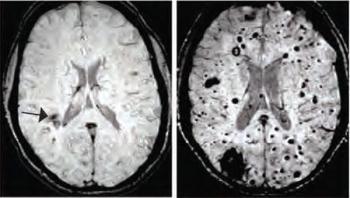

A study in mice and humans suggests that bacteria in the gut can influence the structure of the brain's blood vessels, and may be responsible for producing malformations that can lead to stroke or epilepsy. The research, published in Nature, adds to an emerging picture that connects intestinal microbes and disorders of the nervous system. The study was funded by the National Institute of Neurological Disorders and Stroke (NINDS), a part of the National Institutes of Health (NIH).